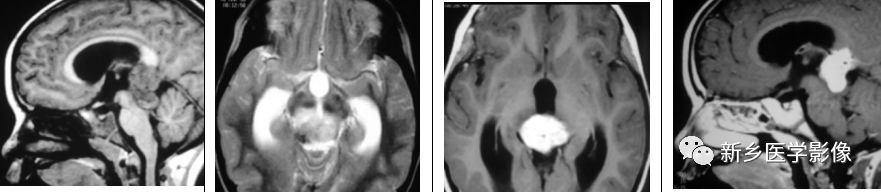

表皮样瘤

颅内表皮样肿瘤为先天性肿瘤,约占颅内肿瘤的1%。其通常发生于脑基底池及脑室,尤其是桥小脑角,鞍旁及第四脑室。它们进入脑脊液空间,产生明显肿块占位效应。在常规MRI上,它们的信号与脑脊液类似,有时,可表现为“脏脑脊液”表现。DWI是鉴别表皮样肿瘤与蛛网膜囊肿的有效方法,通过表观弥散系数反映了表皮样瘤内部的固体性质,而蛛网膜囊肿为纯液。

矢状位及横断位T1WI示松果体区一混杂、高信号肿块,横断位T2WI及FLAIR呈高信号,横断位及矢状位T1WI+C未见明显强化,DWI示呈高信号,符合弥散受限。

脑膜瘤

松果体区脑膜瘤起自中间帆或起自天幕的游离缘。少数情况下,其起自松果内蛛网膜粒包涵体。

矢状位T1WI示松果体区等信号肿块,横断位T2WI及FLAIR呈稍高信号,DWI示呈高信号,低ADC值,符合弥散受限,这是一例不典型脑膜瘤;矢状位、横断位及冠状位,T1WI+C示沿右侧小脑幕明显强化肿块,伴脑膜尾征。